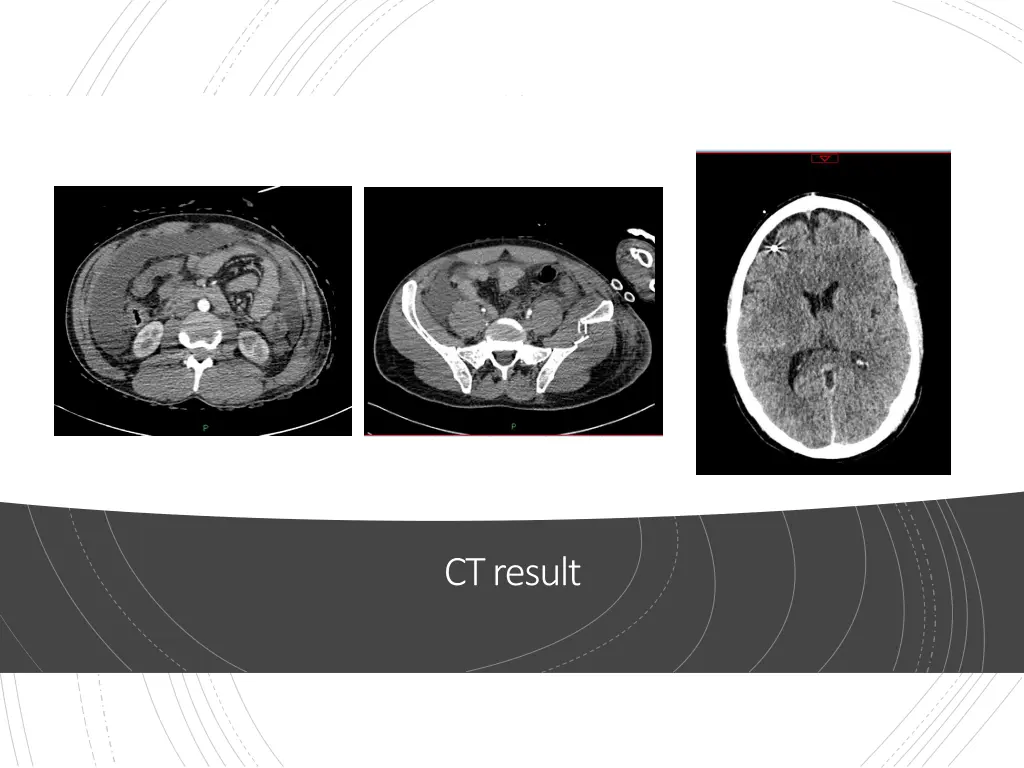

Admission to Intensive Care Neurocritical care Intracrainial Pressure monitor Sedated and ventilated Increasingly unstable CT Scan

Intensive Care Theatre Repair of small bowel perforation Returned to ICU 24hrs to stabilise, reducing organ support Extubated Discharged from ICU to Major Trauma Ward